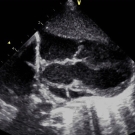

A 20-year-old woman presented for her first prenatal care visit at 32 weeks of gestation. Her pregnancy had been uneventful. An initial fetal ultrasonogram demonstrated an enlarged heart and aortic...

Due to a neonate’s tachypnea and pallor at delivery, echocardiography was done to assess for cardiac lesions, only to find one of the rarest conditions known of cardiac origin, of which requires serious...